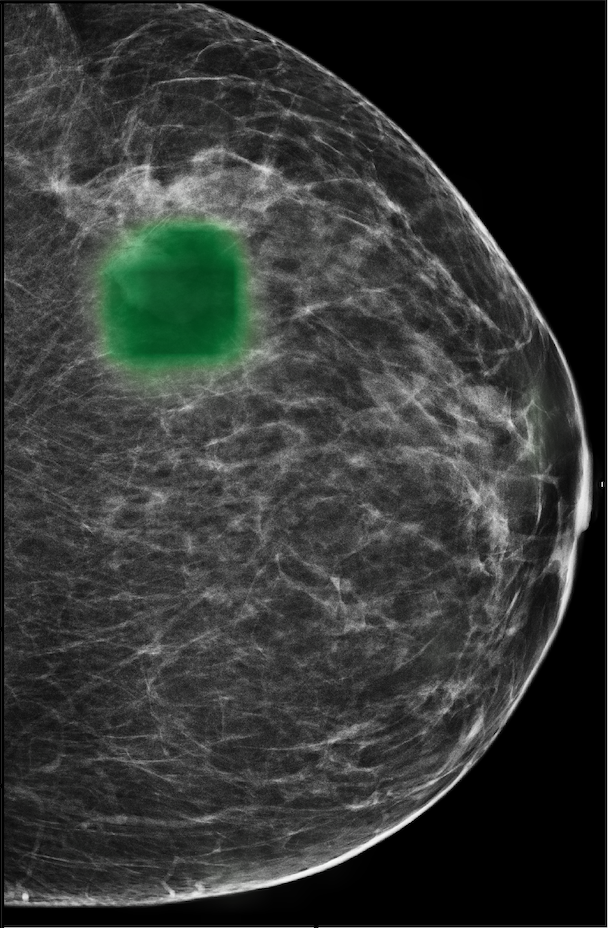

The NYU Breast Cancer Screening Dataset [78] includes 229,426 exams (1,001,093 images) from 141,472 patients.222Our retrospective study was approved by our institutional review board and was compliant with the Health Insurance Portability and Accountability Act. Informed consent was waived. Each exam contains at least four images which correspond to the four standard views used in screening mammography: R-CC (right craniocaudal), L-CC (left craniocaudal), R-MLO (right mediolateral oblique) and L-MLO (left mediolateral oblique). An example is shown in Figure 3.

For all exams matched with biopsies, we asked a group of radiologists (provided with the corresponding pathology reports) to retrospectively indicate the location of the biopsied lesions. This way we obtained the segmentation labels: where if pixel belongs to the benign/malignant findings. An example of such a segmentation is shown in Figure 3. In all experiments (except for experiments in Section 3.6 that assess the benefits of utilizing segmentation labels), segmentation labels are only used for evaluation. We found that, according to the radiologists, approximately of exams were mammographically occult, i.e., the lesions that were biopsied were not visible on mammography, even retrospectively, and were identified using other imaging modalities: ultrasound or MRI.

In Figure 7, we visualize saliency maps for four samples selected from the test set. In the first two examples, the saliency maps are highly activated on the annotated lesions, suggesting that our model is able to detect suspicious lesions without pixel-level supervision. Moreover, the attention is highly concentrated on ROI patches that overlap with the annotated lesions. In the third example, the saliency map for benign findings identifies three abnormalities. Although only the top abnormality was escalated for biopsy and hence annotated by radiologists, the radiologist’s report confirms that the two non-biopsied findings have a high probability of benignity and a low probability of malignancy. In the fourth example, we illustrate a case when there is some level of disagreement between our model and the annotation in the dataset. The malignancy saliency map only highlights part of a large malignant lesion with segmental coarse heterogeneous calcifications. This behavior is related to the design of : a fixed pooling threshold cannot be optimal for all sizes of ROI. The impact of is further studied in 3.6. This example also illustrates that while human experts are asked to annotate the entire lesion, CNNs tend to emphasize only the most informative regions. While no benign lesion is present, the benign saliency map still highlights regions similar to that in the malignancy saliency map, but with a lower probability than the malignancy saliency map. In fact, calcifications with this morphology and distribution can also result from benign pathophysiology [42].